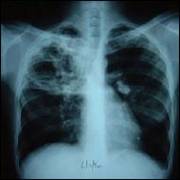

Bolile sistemului respirator

CANCERUL BRONHOPULMONAR

Este o tumoare maligna,cu punct de plecare bronsic.

SIMPTOME simptomele cancerului bronsic,atat cele de debut cat si cele tarzii,sunt in raport cu rectiile pe care le produce tumoarea la nivelul bronhieisi la nivelul parenchimului pulmonar.Unele infectii pot domina tabloul clinic si masca noplasmul.De aceea orice infectie pulmonara persistenta,recidivanta sau rebela la tratament,la un bolnav peste 40 anitrebuie sa sugereze si existenta unui cancer pulmonar.

TRATAMENTULchirurgical estesingurul eficace.Majoritatea bolnavilor ajung prea tirziu la interventia chirurgicala.Tratamentul medical este indicat in formele inoperabiledin cauza metastazelor,varstei inaintate,a complicatiilor.

TUBERCULOZA PULMONARA

Este

o boala infeto-contagioasa provocata de bacilul Koch,afectand organismul in

intregime,interesind cu precadere plamanul si avand de obicei o evolutie

cronica,pe parcursul careia se deosebesc 2 etape: tuberculoza primara si

tuberculoza secundara. Tuberculoza este cauzata de o bacterie (Mycobacterium

tuberculosis). La nivel mondial se estimeaza aproximativ 2 miliarde de

purtatori. Ea afecteaza de obicei plamanii, dar si alte parti ale organismului,

mai ales sistemul osos si creierul. Trebuie facuta diferenta intre infectie si

boala. Persoanele care sunt doar infectate nu se simt bolnave si nu au

simptome. Infectia se poate prelungi toata viata, fara ca boala sa se

declanseze. Putem contracta tuberculoza la orice varsa. Aceasta se transmite

rapid, in special in randul populatiei defavorizate, cu accesibilitate redusa

la medic si prost hranita.